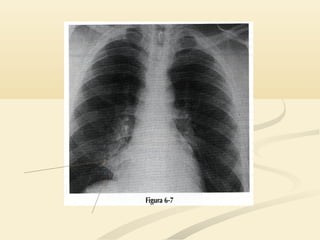

 La consolidación del LSD causará un signo de la siluetaLa consolidación del LSD causará un signo de la silueta

en el borde cardíaco derecho superior y en la interfaseen el borde cardíaco derecho superior y en la interfase

traqueopulmonar derecha.traqueopulmonar derecha.

 El LSDocupa el tórax anterior y medio por encima deEl LSD ocupa el tórax anterior y medio por encima de la cisura menor.la cisura menor.  La consolidación del LSD causará un signo de la siluetaLa consolidación del LSD causará un signo de la silueta en el borde cardíaco derecho superior y en la interfaseen el borde cardíaco derecho superior y en la interfase traqueopulmonar derecha.traqueopulmonar derecha.